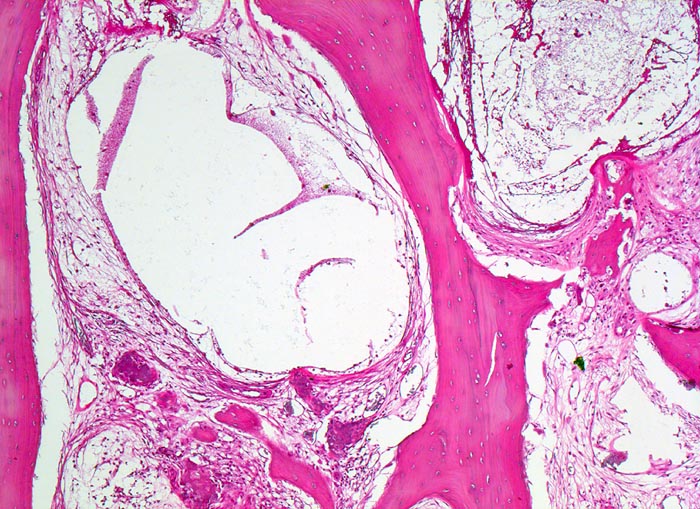

aseptische Femurkopfnekrose

Knochen, Femurkopf

Ausschnitt aus der Nekrosezone: osteoklastische Resorption eines sequestrierten Spongiosabälkchens. In den nekrotischen Markräumen haben sich pseudozystische Hohlräume gebildet. Das nekrotische Knochenmark wird ersetzt durch lockeres gefässhaltiges Bindegewebe.

Der Patient ist Gastwirt von Beruf und klagt über rasch zunehmende Schmerzen im rechten Hüftgelenk, die auch nachts auftreten. Aufgrund der invalidisierenden Schmerzen wird eine Endoprothese eingesetzt.